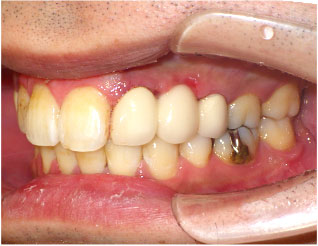

- ブリッジ 症例写真 B-0093スタンダードジルコニア9本、スタンダードジルコニア7本 男性モニターの方です。

Before

After詳細はコチラ

セラミック法によるブリッジ治療の症例

- No. B-0093

施術 スタンダードジルコニア9本、スタンダードジルコニア7本 - コメント

この方は前歯の歯並びと奥歯の虫歯、欠損の治療を希望されました。

前歯の歯並びはセラミック法で治療しました。

奥歯の欠損はブリッジで治療しました。

また、下の前歯も歯周病で1本抜歯になりましたのでその部分もブリッジ治療しています。

当院ではこの様にいろいろな歯のお悩みがあっても同時進行で治療する事が可能です。